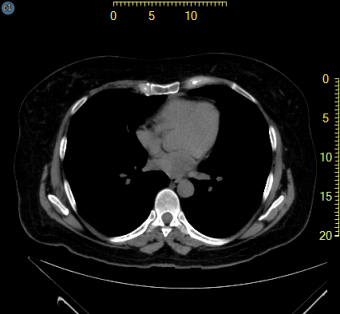

Ruler overlays appearing on the outside of the image frame exist for all calibrated images as shown highlighted in yellow below. The user is able to assign the location of the rulers, and whether they exist for the vertical, horizontal or both planes.

Left + Top scale |

Show a scale on the left and one on the top |